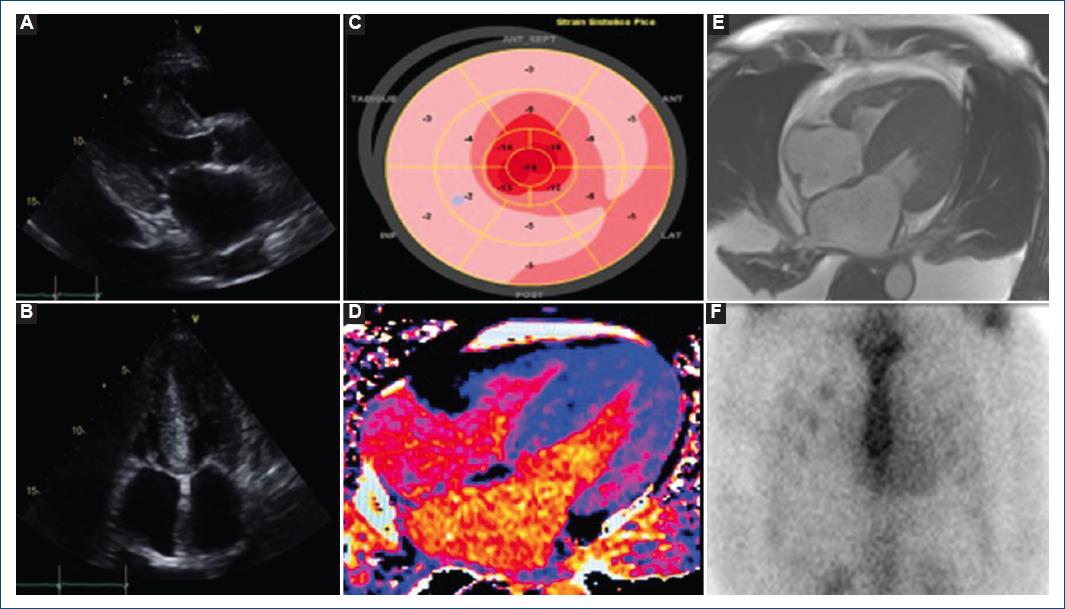

Considering the presence of numerous indicative signs of amyloidosis because of multiple organ-damage involvements, an echocardiogram was undertaken, uncovering marked myocardial hypertrophy (Fig. 2A and B), a septal mottled pattern, and biauricular dilation. In addition, distinctive bull's eye or Japan flag patterns (apical sparing) were discerned in strain imaging (Fig. 2C). To further enhance the diagnostic approach, cardiac magnetic resonance imaging (CMRI) was executed, revealing noteworthy myocardial hypertrophy, diffuse transmural late gadolinium enhancement in the right ventricular free wall, a left ventricular ejection fraction of 63%, right ventricular ejection fraction of 55%, mild pericardial effusion, and a substantial increase in extracellular volume of 71% (Fig. 2D and E), thereby satisfying diagnostic criteria through both modalities. Furthermore, to differentiate between AL and ATTR amyloidosis, we performed a 99m Technetium-pyrophosphate (99mTc-PYP) scan, resulting in absent myocardial uptake (Fig. 2F), discarding ATTR phenotype.

Figure 2 A: long-axis parasternal view in echocardiogram with marked myocardial hypertrophy. B: four-chamber view in echocardiogram with important septal hypertrophy, as well as rough, mottled pattern, and biauricular dilation. C: typical apical sparing in Strain imaging. D: T2 mapping with an increase in investment times, suggesting diffuse amyloidosis with high extracellular water/protein volume. E: cardiac magnetic resonance imaging with marked myocardial hypertrophy, diffuse transmural late gadolinium enhancement in the right ventricular free wall, mild pericardial effusion, and a substantial increase in extracellular volume. F: 99m technetium-pyrophosphate scan with absent myocardial uptake.